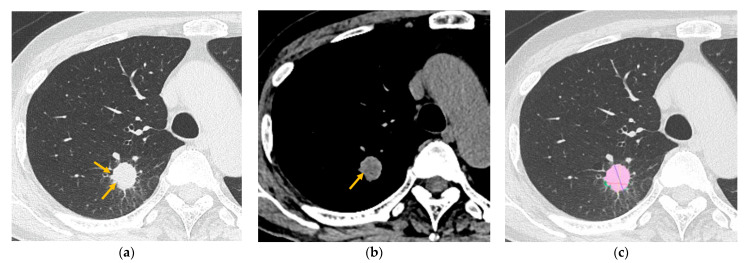

Background/objectives: Spread through air spaces (STAS) is defined as the spread of tumor cells into the parenchymal alveolar space beyond the margins of the main tumor, and it is associated with worse clinical outcomes in resected lung adenocarcinoma. This study aimed to evaluate the preoperative computed tomography (CT) findings of primary lung adenocarcinoma in surgically resected T1 cases and to compare CT findings with and without STAS.

Methods: A total of 145 patients were included in this study. The following factors were evaluated on CT images: nodule type (pure ground-glass nodule [GGN], part-solid nodule, or solid nodule), margin (smooth or irregular), the presence of lobulation, spicula, cavity, calcification, central low attenuation, peripheral opacity (well-defined or ill-defined), air bronchogram, satellite lesions, pleural retraction, pulmonary emphysema, and interstitial pneumonia; CT values (maximum, minimum, and mean); volume (tumor and solid component); and diameter (tumor and solid component). CT criteria were compared between the presence and absence of STAS.

Results: Lobulation and central low attenuation were significantly more frequent in patients with STAS (p < 0.05). The mean CT value, and the volume, rate, and diameter of the solid component were significantly larger in cases with STAS (p < 0.05). A multiple logistic regression analysis identified central low attenuation as an indicator of the presence of STAS (p < 0.001; odds ratio, 3.993; 95% confidence interval, 1.993-8.001).

Conclusions: Quantitative and qualitative analyses are useful for differentiating between the presence and absence of STAS.